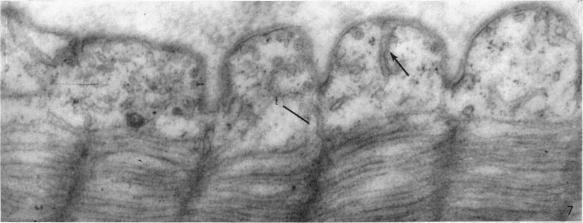

Fine structure of the muscular wall of rat pulmonary veins.

J Anat. 1968 Sep;103(Pt 2):345-57.